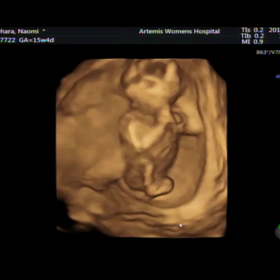

15w4d 3D、4Dエコー動画 リラックマタウンカフェ